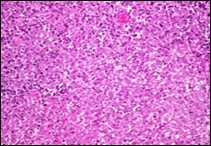

Ultrastructural evaluation is devoid of pertinent cellular features. However, modified endothelial cells, smooth muscle cells, striated muscle cells, histiocyte- like cells, fibroblast- like cells and miniature, interdigitating cellular processes conjoined by desmosome- like junctions are discerned5, 6. Figure 1, Figure 2, Figure 3, Figure 4, Figure 5, Figure 6, Figure 7, Figure 8.

Figure 4.Angiomatoid fibrous histiocytoma exhibiting spherical to elliptical cells comingled with abundant vascularized stroma and a peripheral accumulation of small lymphocytes with plasma cells 11.